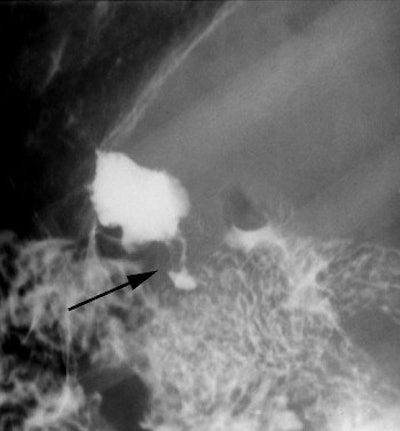

For gastrointestinal injuries, the key findings range from a narrowing of the pyloric canal with distension of the duodenum’s first and second portions, fistulae, strictures, and erosions in the esophageal lining. A variety of modalities can document such signs. Rha’s team used delayed-compression spot radiography to document duodenal diaphragm, and confirmed it with exploratory laparoscopy.

| Upper gastrointestinal radiograph shows smooth narrowing of pyloric canal and marked distension of first and second portion of duodenum (D). Also, note marked passage disturbance at third portion of duodenum to distal bowel loops (arrow). S is the stomach. Rha, SE, Lee JH, Lee SY, Park, SM, "Duodenal diaphragm associated with long-term use of nonsteroidal anti-inflammatory drugs: a rare cause of duodenal obstruction in an adult," (AJR 2000, Vol. 175, pp. 920-921). |